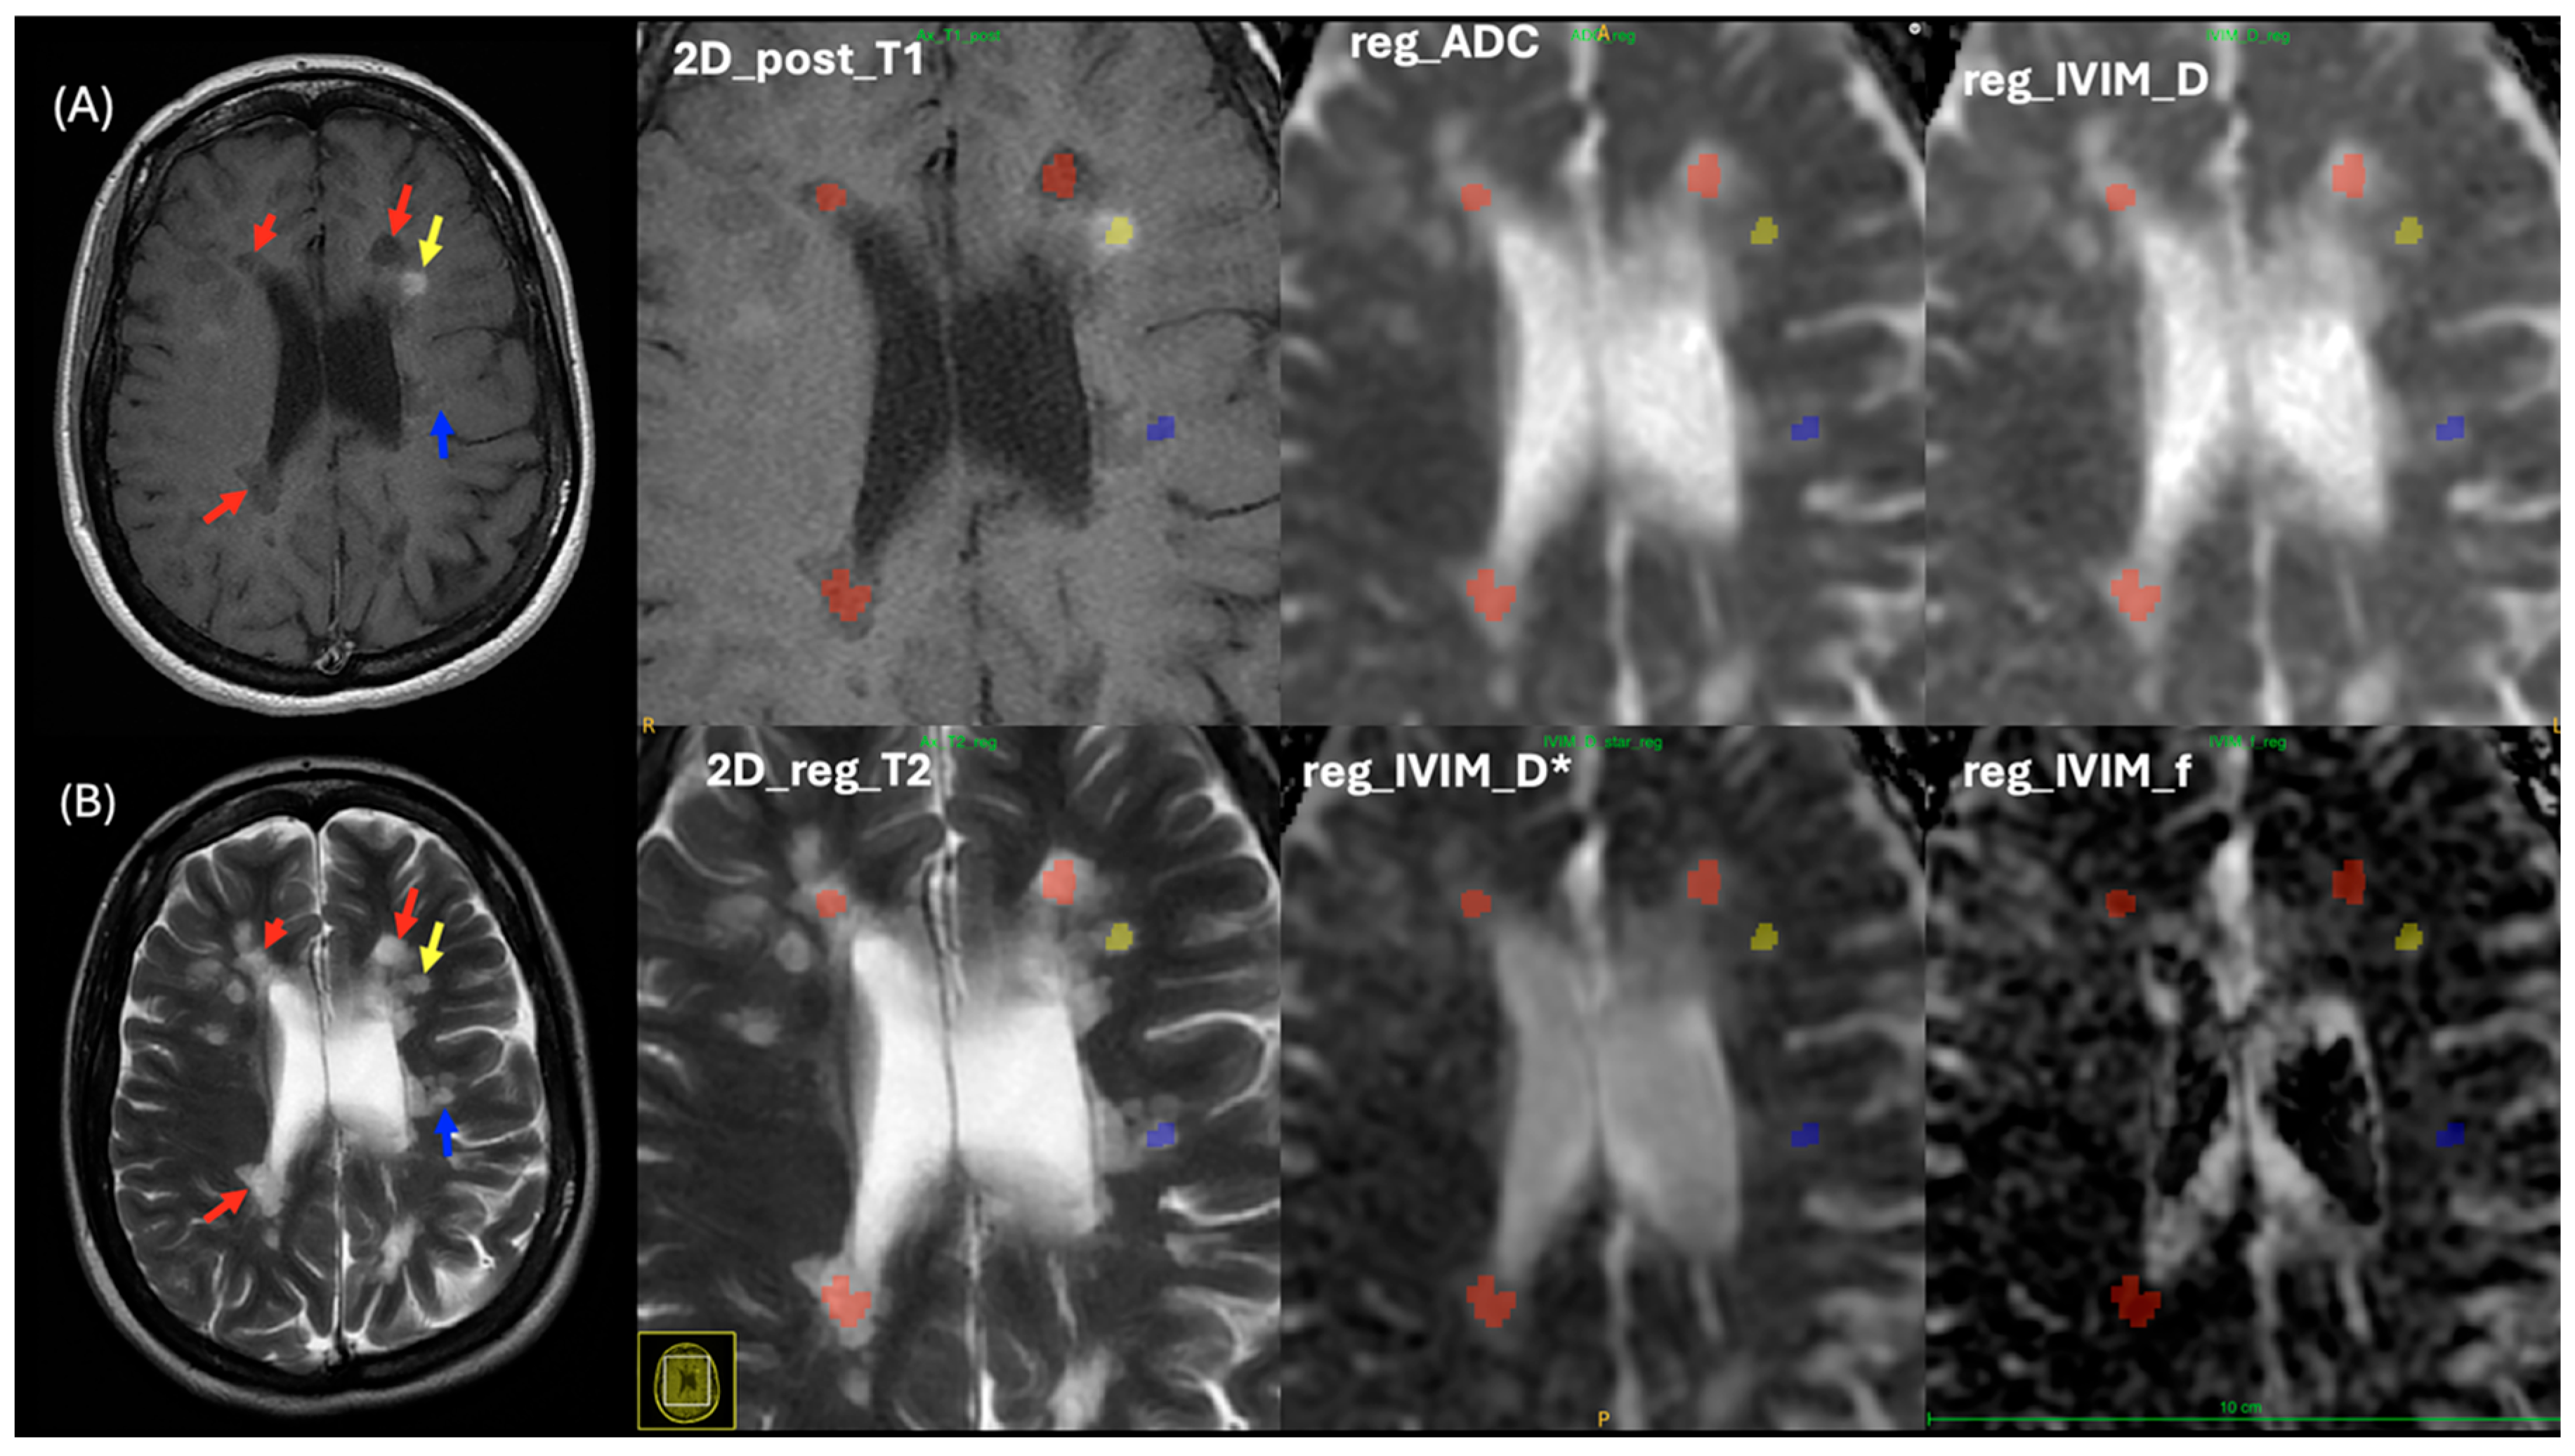

2.2. Lesion Analysis

2.4. MRI Processing